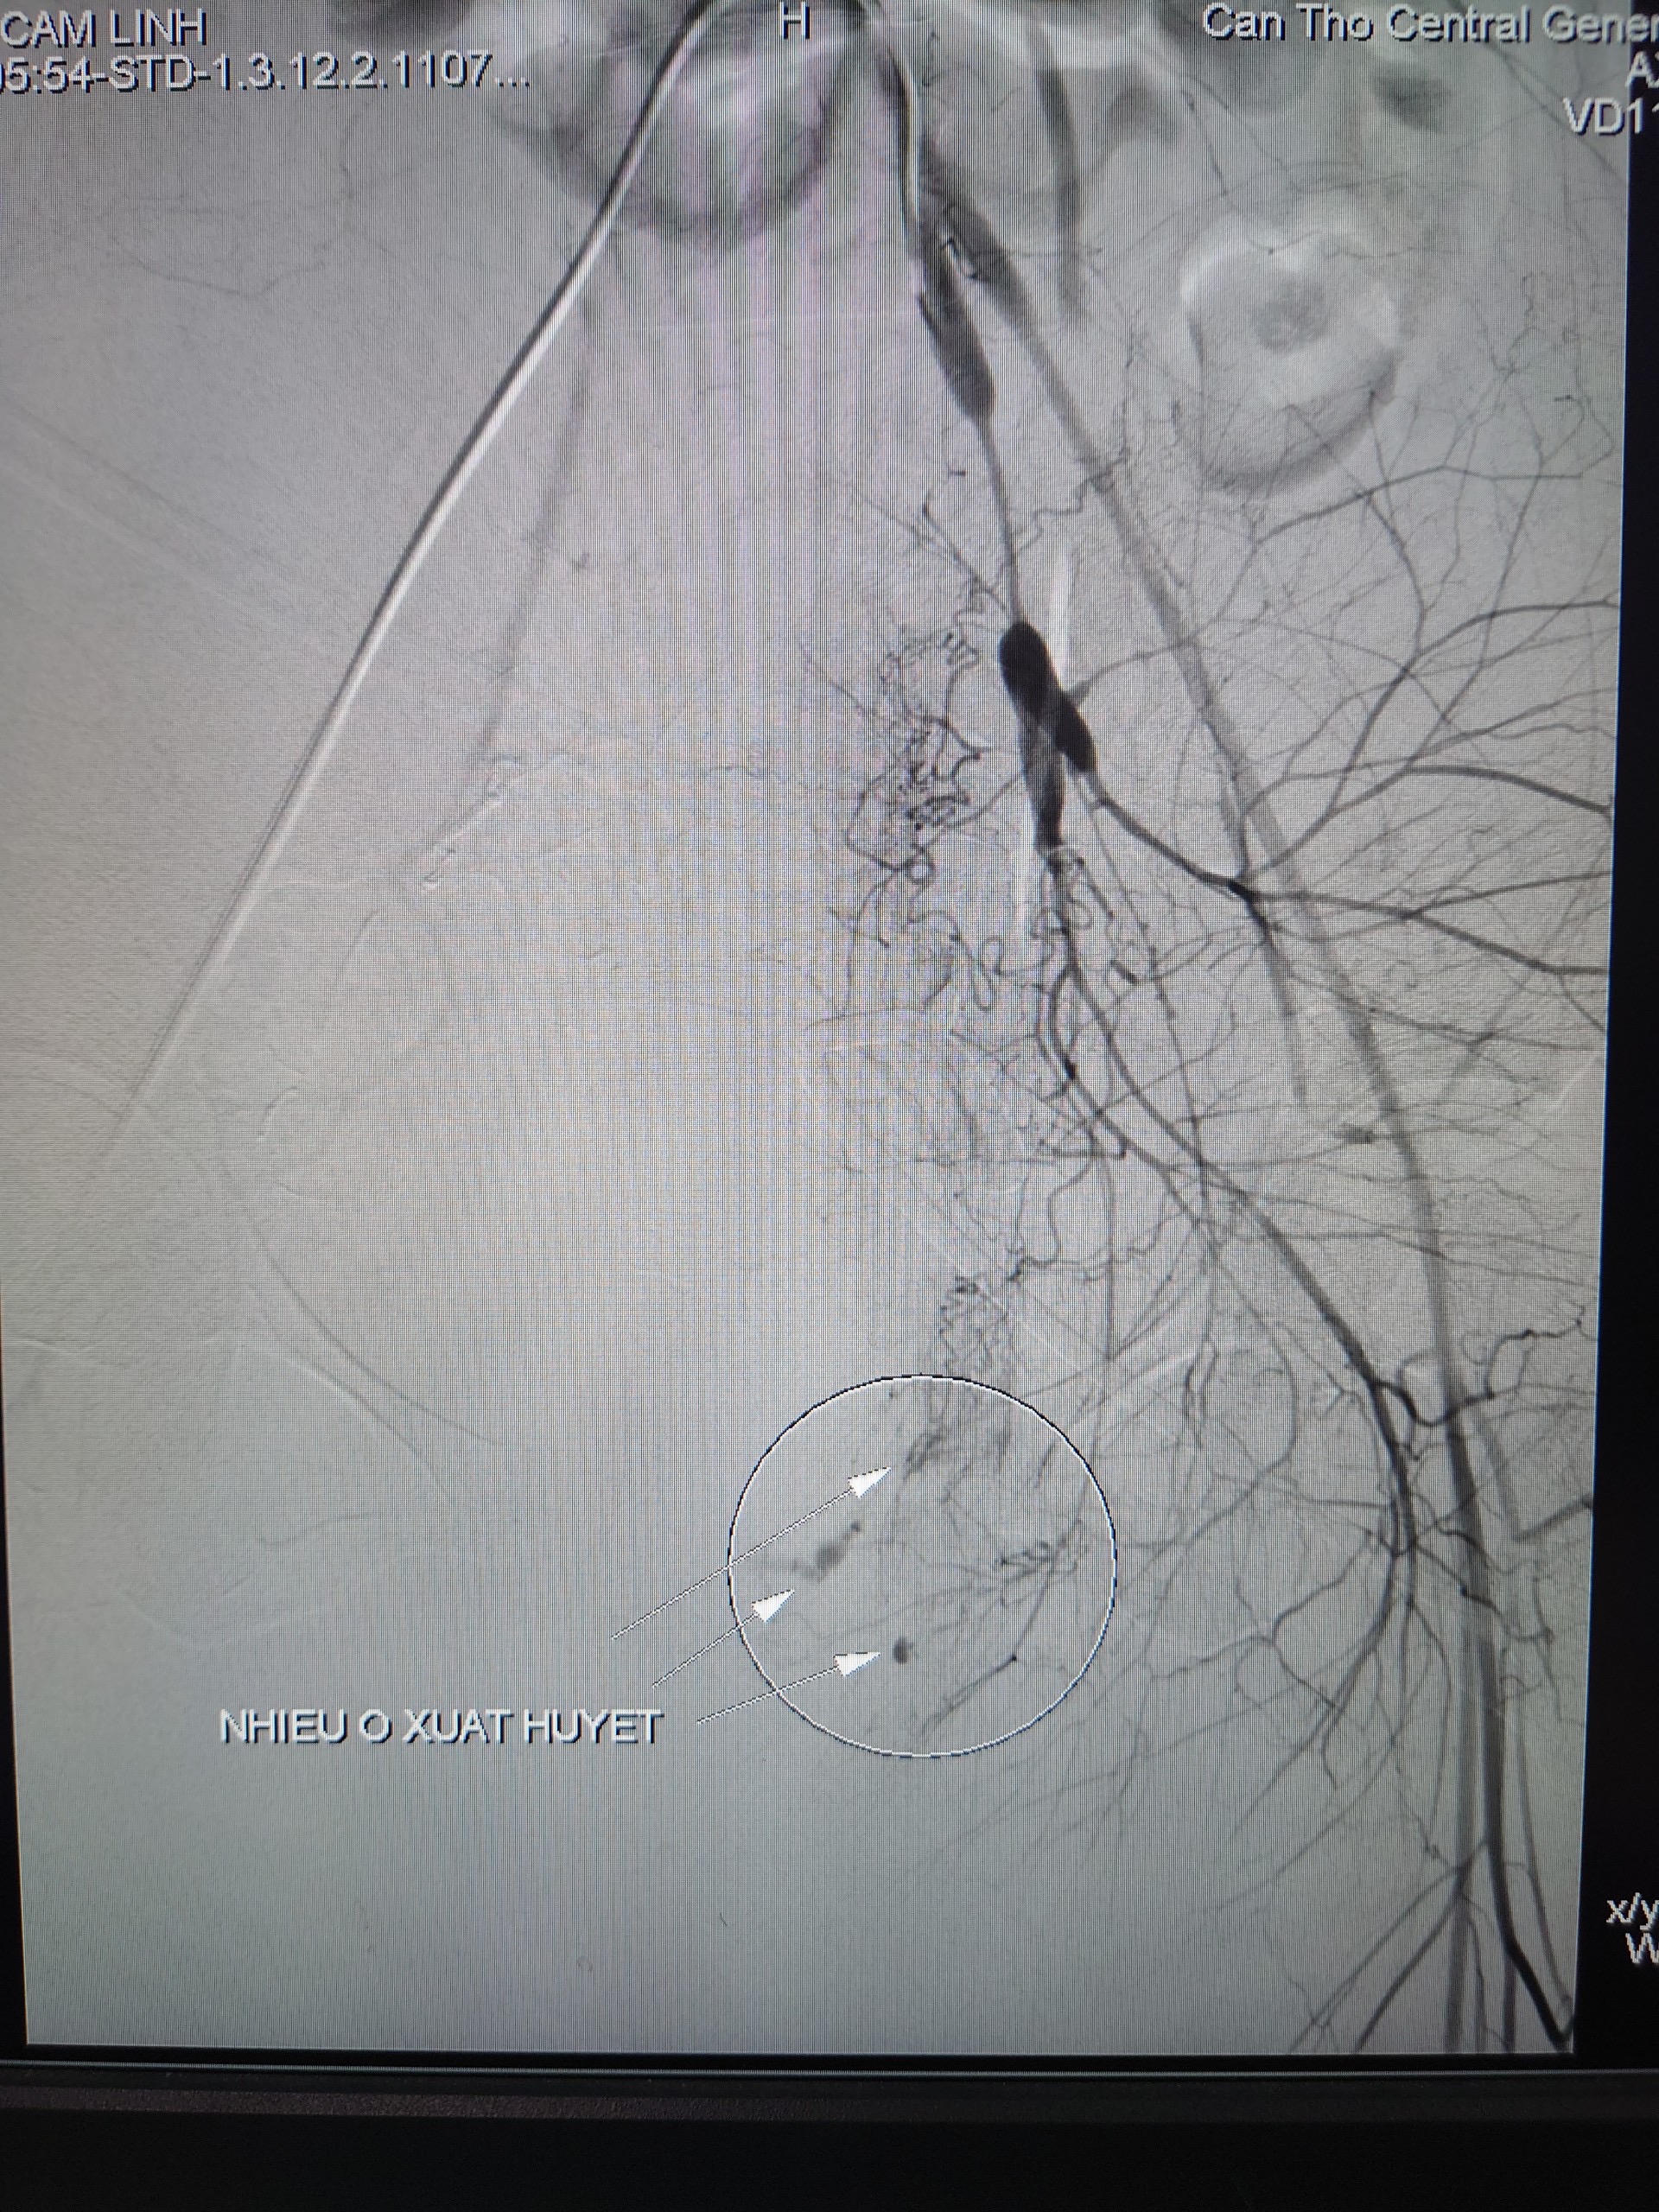

![]() |

Hình ảnh chụp mạch máu số hóa xóa nền nhiều ổ xuất huyết |